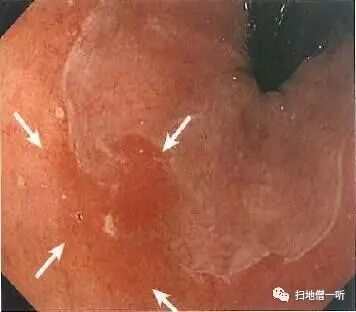

A:胃癌在图4及图5。HP除菌后胃癌。

背景粘膜为O-3型萎缩并肠化。除菌后出现地图状粘膜及多发凹陷性发红区域,如此背景下良性糜烂与癌难以分辨。图4中胃底大弯后壁片状发红较为显著。图5为接近观察可见周围粘膜有淡黄色调感,警惕癌区。

靛胭脂喷洒后变换角度从切线位观察可见凹陷面更加明显,边界不整。

最终病理诊断:

胃体中部大弯后壁,O-IIc,10mm,tub1,T1a (M),UL(-)

小结:

• HP除菌后多发红色凹陷中重点观察边界不整的凹陷

• 靛胭脂有助于鉴别发红的良恶性凹陷